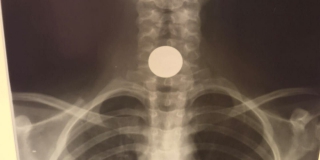

Государственным учреждением будет закуплено порядка 10 тысяч одноразовых костюмов для работ в очагах коронавирусной инфекции. Их можно будет использовать как в операционных, так и в амбулатории. К ним требуется такое же количество нестерильных медицинских масок. Кроме этого, отдельно будет закуплено порядка 5 тысяч «масок фильтрующих с классом защиты ffp3» и 3 тысячи защитных очков.

Разумеется, все товары произведены в Китае. Средства медицинской защиты будут поставляться по следующим ценам: костюмы – 3,5 тысячи рублей за штуку; нестерильная маска – 425 рублей за штуку; фильтрующая маска 690 рублей; очки по 720 рублей.